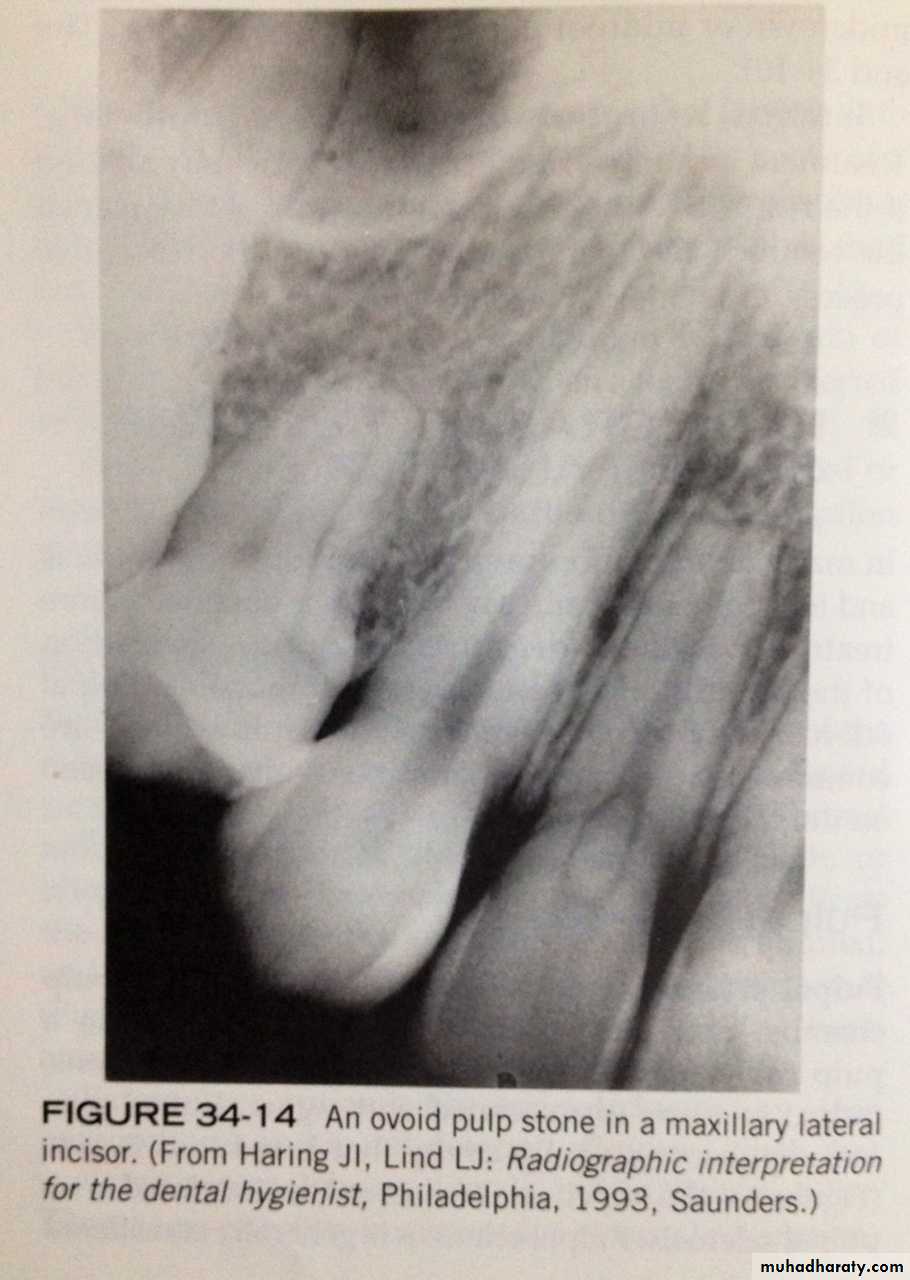

pulp stones- are calcifications that are found in pulp chamber or pulp canal. the cause unknown.

- On dental radiograph: pulp stone appear as round, ovoid or cylindrical radiopacities. do not cause symptoms and do not require treatment.